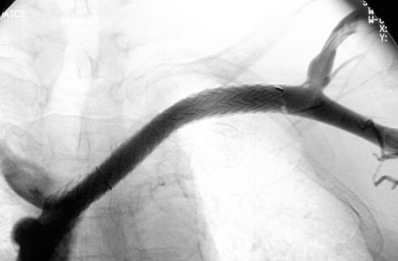

67岁女性,慢性肾功能衰竭和糖尿病历史,自体左上肢头臂动脉-静脉瘘重建手术及血透23个月,现左上肢肿胀 ![]() 血管造影发现左锁骨下静脉闭塞,侧支循环较少。 ![]() 8mm直径球囊扩张后,仍然有至少7个厘米的狭窄。但下腔静脉脉内没有血栓。可以选择12mm直径球囊扩张、支撑架植入或外科治疗,或者就这样不管了,等待血栓自溶。 病人是症状性肢体肿胀,如果不管,透析时可能造成静脉血流增加和压力增高或影响透析的效果。改用12mm直径球囊可能会比放支撑架更危险,主要担心血管会破裂,可能疗效一样不会持久。尽管报告外科可能成功的治疗这类疾病,但即贵也风险。扩张后静脉明显回缩,放支撑架侵入性最小,病人耐受,成功率高[1,2],Kovalik[3]报道,单纯扩张平均2.9月再阻塞。Wallstent好于单纯的PTA,但是支撑架6~12个月可能再阻塞。

![]() 病人最终选择了10mm直径,9cm长的Viatorr覆膜支撑架,其中覆膜部分为7cm,2cm为裸支撑架。释放杆为10F,41厘米长。支撑架前端裸支撑架部分进入上腔静脉,覆膜部分在狭窄段锁骨下静脉。释放支撑架后,用扩张球囊扩张到10mm。最后影像如上图所示。3个月后血管造影发现,在支撑架远心端的支撑架未覆盖的血管有轻度狭窄。未做处理。